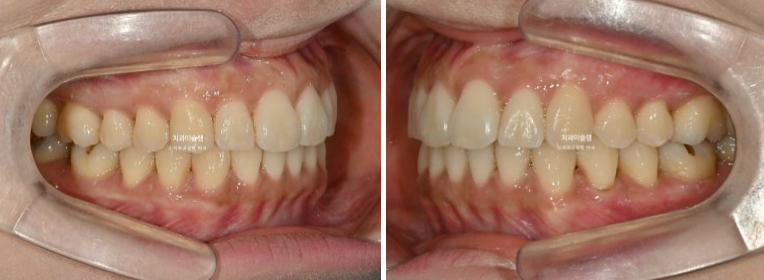

이제 전후 비교 보겠습니다.

23.08~25.11

총 치료기간은 2년 3개월이고 재제작 2회입니다.

현재는 비베라를 매일 잘 때만 끼면서 결과 유지중입니다.